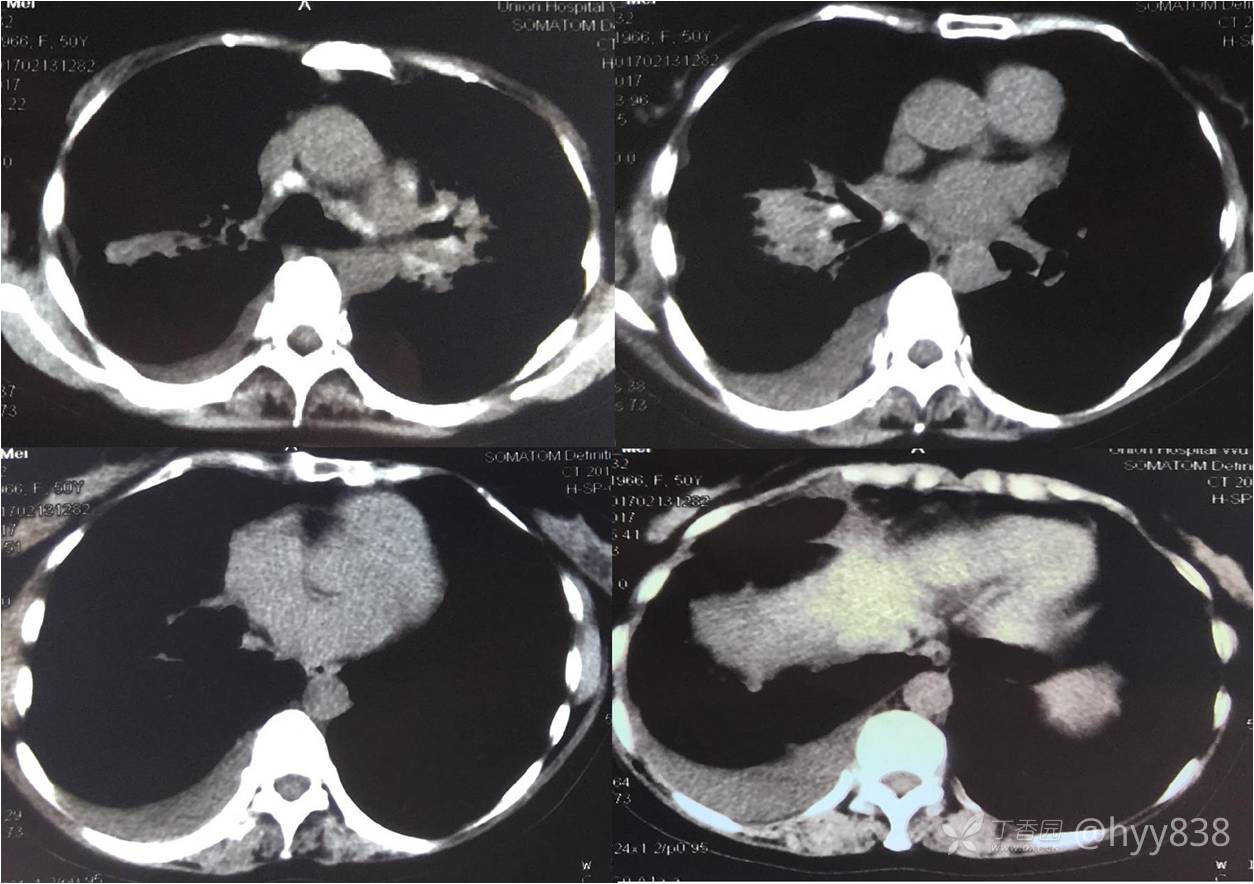

次年行CT复查,病灶进展

增强